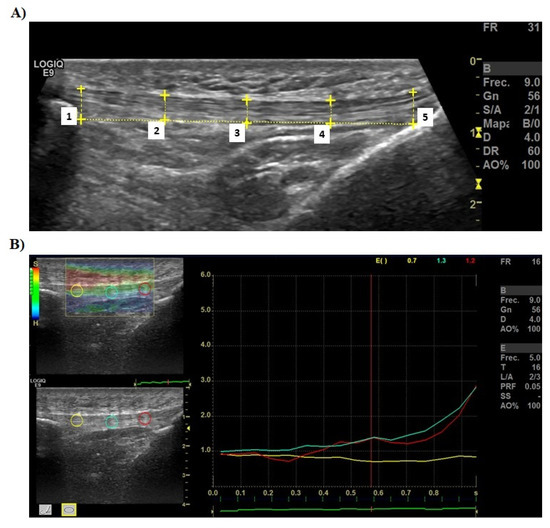

2.5. Thickness of PT Assessment

2.6. Elastic Properties of PT Assessment